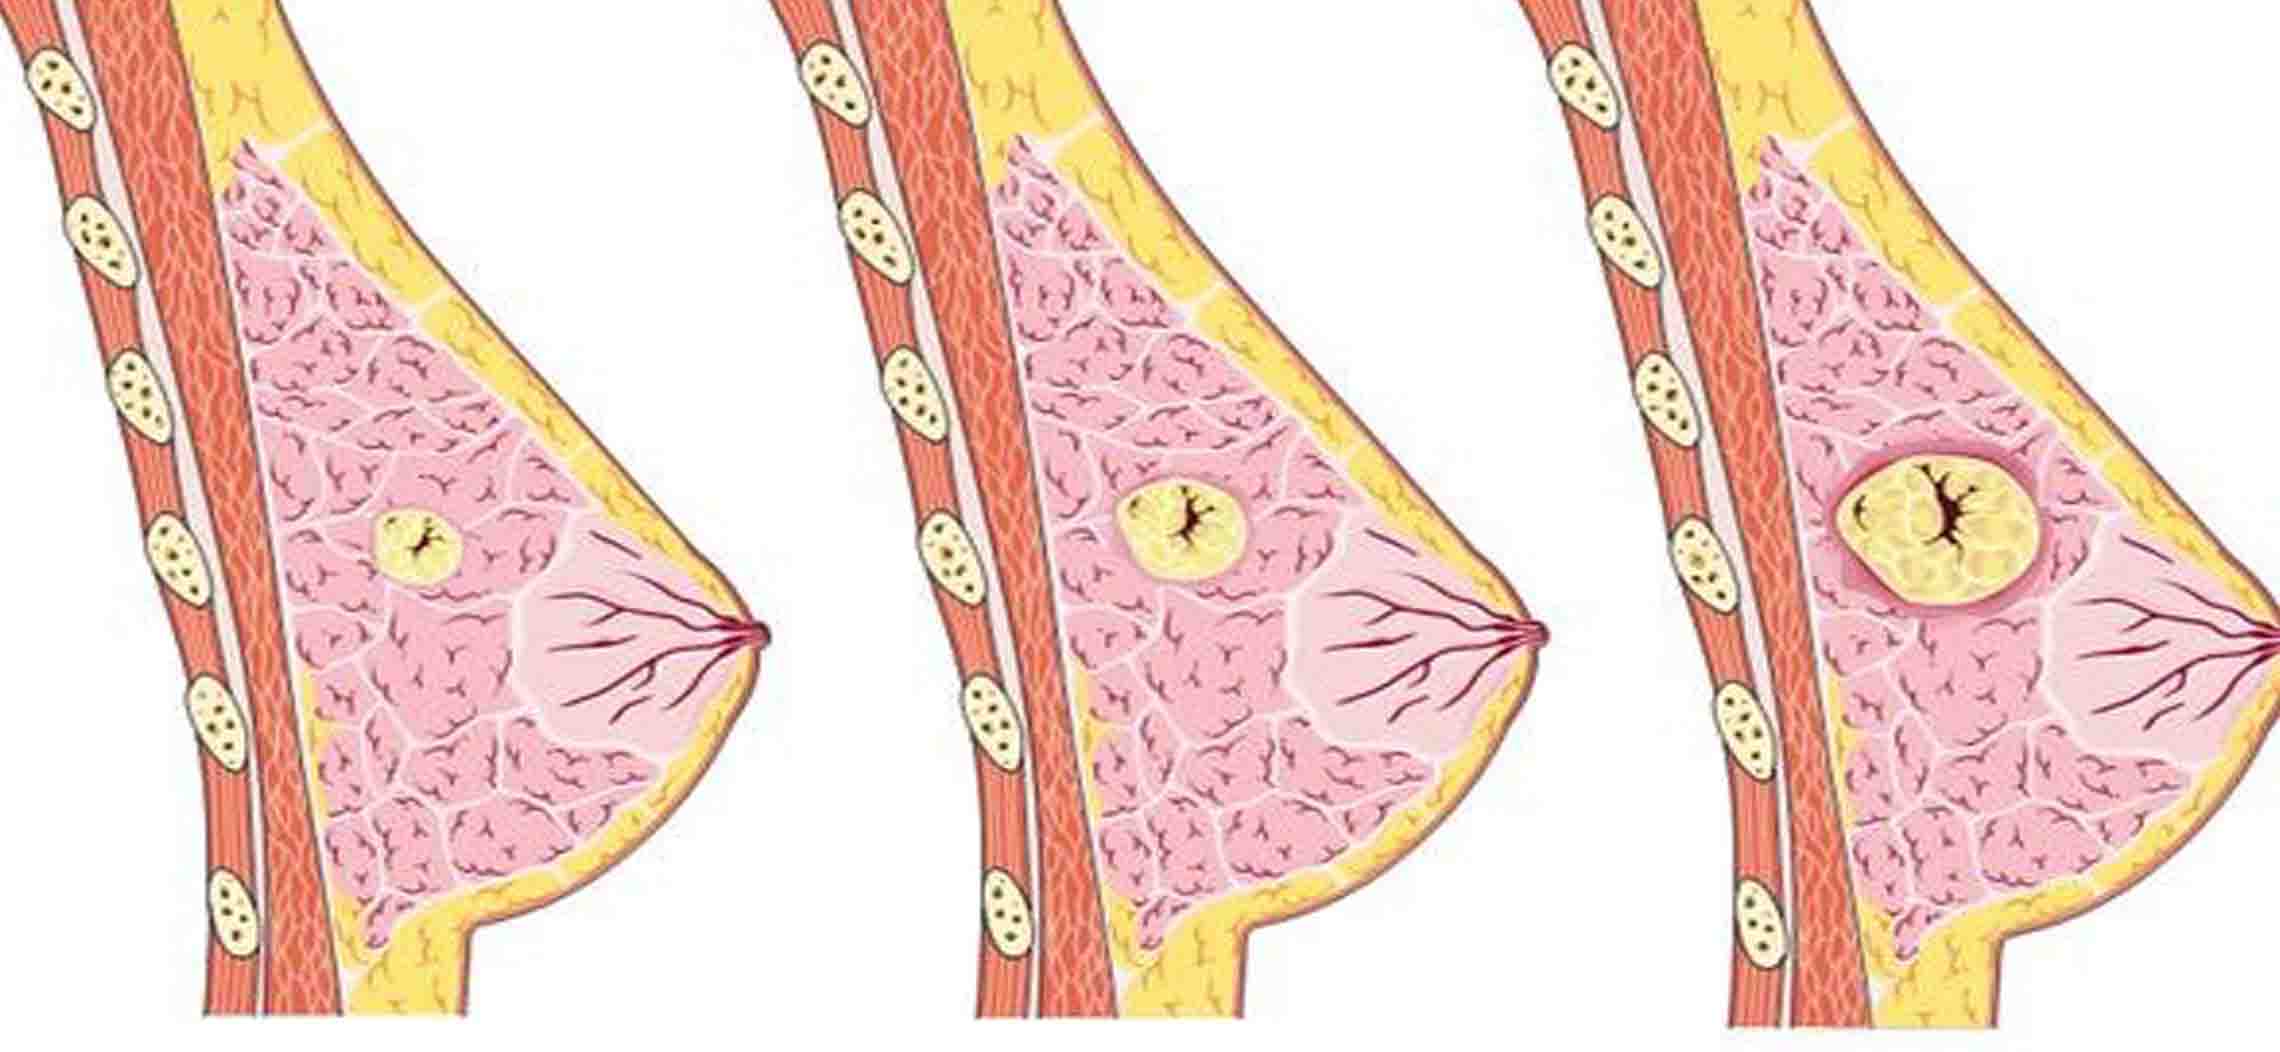

Уплотнения в груди могут быть вызваны различными причинами, включая кисты, фиброаденомы или инфекционные процессы. Важно понимать, как правильно подходить к их лечению и когда обращаться к врачу. Следующие советы помогут вам разобраться в этом вопросе и обеспечить здоровье своей груди.